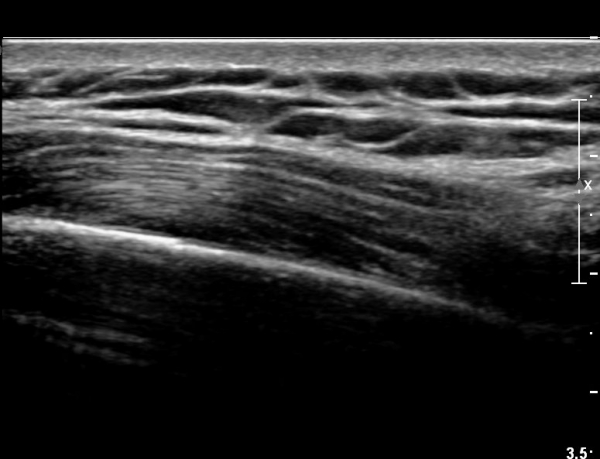

8¹øÂ° °¥ºñ»À Á¾´Ü¸é°Ë»ç»ó °¥ºñ»À Ç¥ÃþÀ¸·Î Àú¿¡ÄÚ ºÎÁ¾°ú °¥ºñ»À Ç¥Ãþ¿¡ ÀÖ´Â

±Ù¼¶À¯µéÀÌ Ç¥ÃþÀ¸·Î ¹Ð·ÁÀÖ´Â °ÍÀÌ °üÂûµÇ°í(»çÁø 1, 2) °¥ºñ»À ÇÇÁú°ñ ¿¬¼Ó¼º

´ÜÀýÀÌ ÀǽɵȴÙ(»çÁø 2).